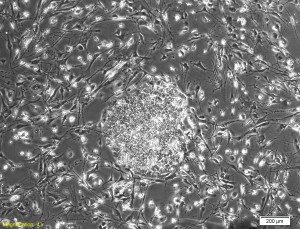

Colonia incipiente de iPSC luego de la reprogramación